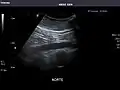

Aorta: Visualized portions normal in caliber, 16 x 15 mm.

Aorta